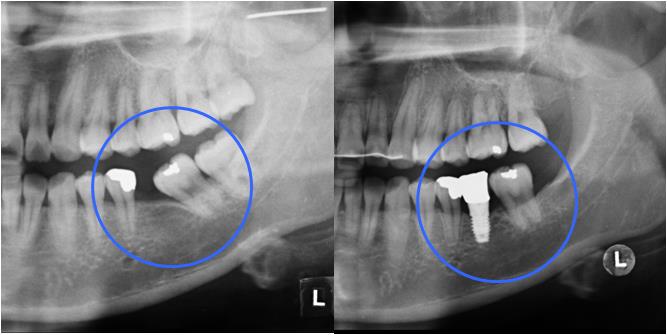

ºÎÁ¤±³ÇÕÀÌ Æ¯Á¤ ºÎÀ§¿¡ ±¹ÇѵǾî ÀÖ´Â °æ¿ì ƯÁ¤ Ä¡¾Æ¿¡¸¸ ÀåÄ¡¸¦ ºÎÂøÇÏ¿© ±³Á¤ ÇÏ´Â °æ¿ìµµ ÀÖ½À´Ï´Ù. Ʋ¾îÁ®ÀÖ´Â ¾Õ´Ï¸¸ ºÎºÐÀûÀ¸·Î °í¸£°Ô ¹è¿Çϰųª(±×¸²3) º¸Ã¶(ÀÓÇöõÆ®)À» À§ÇØ ¾²·¯Áø ¾î±Ý´Ï¸¦ ¹Ù·Î ¼¼¿ì´Â °æ¿ì(±×¸²4), »ó½ÇµÈ ´ëÇÕÄ¡ ¶§¹®¿¡ Á¤ÃâµÈ ¾î±Ý´Ï¸¦ ¾ÐÇϽÃŰ´Â Ä¡·á°¡ ´ëÇ¥ÀûÀÎ °æ¿ìÀÔ´Ï´Ù(±×¸²5). Áõ·ÊÀÇ ³À̵µ³ª ¹è¿»óÅ¿¡ µû¶ó Åë»ó 6°³¿ù ³»¿ÜÀÇ ±â°£ÀÌ ÇÊ¿äÇÕ´Ï´Ù.

| | ±×¸²5 |